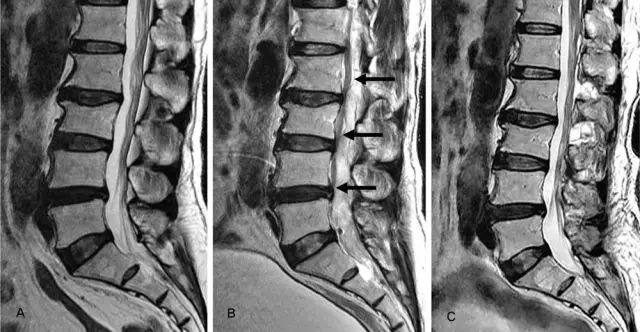

颈部磁共振显示

椎管硬膜外血肿需要行手术治疗

简单的说也就是

血管破裂压迫神经导致了开头说的症状